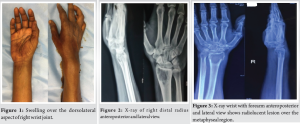

A 44-year-old male presented with complaints of right wrist pain and swelling (Fig. 1) for the past 3 months. He was apparently normal before 3 months. After he developed pain over the right lower forearm which was insidious in onset, non-progressive in nature, dull aching type, non-radiating, aggravated by movements and work relieved by medications. There was no past, family history of note and he was taking no regular medications. On examination of right wrist, diffuse swelling was present just proximal to wrist crease. Tenderness and bony thickening were present over the distal radius.

X-ray of right wrist taken at the time of onset of symptoms – 3 months before presentation (Fig. 2) showed solitary, radiolucent, eccentric lesion over epiphysis and metaphyseal region of right distal radius with narrow zone of transition, with thin cortex. Distal radiocarpal articular surface was maintained. X-ray taken at the time of presentation (Fig. 3) showed the same findings but with additional break in the cortex over medial and lateral aspect of distal radius.